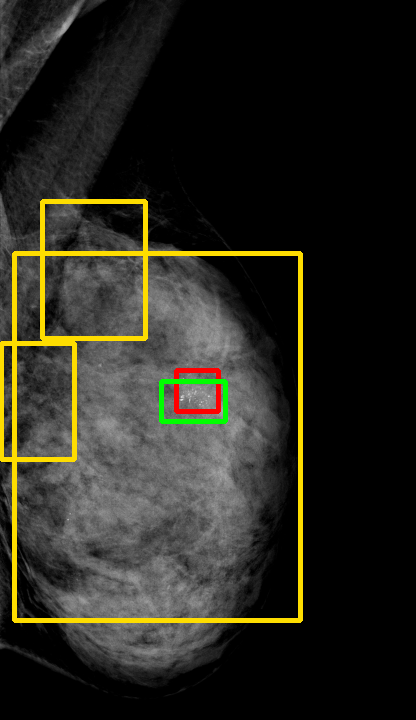

UDA has been extensively studied in case of natural images, utilizing techniques such as adversarial learning [21],pseudo-label training [6, 21, 40], image-to-image translation [40], graph reasoning [20], and adaptive mean Teacher training [6], improving domain adaptation efficiency of object detectors. Recently multiple works focused on using Mask autoencoders (MAE) methods in large-scale pretraining for vision models, involving masking parts of input and reconstructing them [12, 33]. However, these approaches overlook domain shifts. Alternatively, widespread utilization of Teacher-Student models, wherein a Teacher provides pseudo-labels for target domain (unlabeled images) to supervise a Student model, leads to notable adaptation improvements [40, 43]. However, these techniques face the challenge of incorrect predictions and excessive false positives per image due to low-quality pseudo-labels, particularly for medical imaging problems. Pseudo-labels are filtered from the Teacher model’s outputs based on the confidence score threshold. Selecting numerous pseudo-labels with low thresholds leads to inclusion of incorrect predictions, and compromising performance. Conversely, higher thresholds yield a limited number of pseudo-boxes, resulting in sub-optimal supervision. Existing Teacher-Student models often produce pseudo-labels riddled with errors and false positives, as illustrated in Fig. 1(a) and Fig. 1(b). Though [21, 40, 43] utilize techniques like adversarial alignment, weak-strong augmentation, and selective retraining of Student model to minimize the false positives in pseudo-labels, these approaches fail on medical images.

Contributions of this work. We note that screening mammography inherently differs from natural images, with breast abnormalities such as masses, asymmetries, and micro-calcifications, typically much smaller in comparison to the salient objects present in natural images, emphasizing the need for approaches specific to this problem. To address these issues, we make following contributions in this work: (1) We introduce D-MASTER, a transformer-based Domain-invariant Mask Annealed Student Teacher Autoencoder Framework for cross-domain breast cancer detection from mammograms (BCDM), integrating a novel mask-annealing technique and adaptive confidence refinement module. Unlike pretraining with mask autoencoders (MAEs) [12], leveraging massive datasets for training and then fine-tuning on smaller datasets, we present a novel learnable masking technique for the MAE branch that generates masks of different complexities, which are reconstructed by the DefDETR [44] encoder and decoder. Our approach, as a self-supervised task on target images, enables the encoder to acquire domain-invariant features and learn better target representations as shown in Fig. 1(c). (2) In Teacher-Student model, since the pseudo-label noise generated by the Teacher affects the Student model severely, we propose an adaptive confidence refinement module that progressively restricts the confidence metric for pseudo-label filtering. During the initial adaptation phase, soft confidence is applied allowing more pseudo-labels to learn better target representations. Subsequently, as confidence gradually increases, the focus shifts towards enhancing detection accuracy by prioritizing more reliable pseudo-labels. (3) We release a bounding box annotated subset of 1000 mammograms from the RSNA Breast Screening Dataset (referred to as RSNA-BSD1K) to support further research in BCDM. (4) We setup a new state-of-the-art (SOTA) in detection accuracy for UDA settings. We report a sensitivity of 0.74 on INBreast [25] and 0.51 on DDSM [18] at 0.3 FPI, compared to 0.61 and 0.44 using current SOTA respectively. Significant performance gains are also observed on our in-house and RSNA-BSD1K datasets.